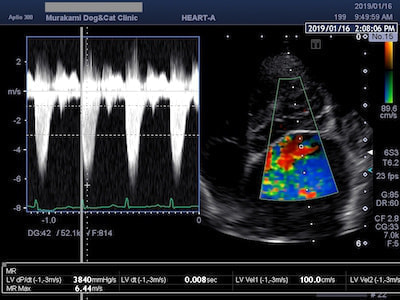

三尖弁閉鎖不全症

僧帽弁閉鎖不全症と同様、弁が正常に閉じなくなることにより三尖弁逆流を引き起こす疾患です。原因は三尖弁の問題だけではなく、肺高血圧症に起因したものが多く、適切な治療には肺高血圧症の原因を鑑別することが重要となります。小型犬では僧帽弁閉鎖不全症に続発した二次性の肺高血圧症が多いと言われていますが、肺血栓塞栓症や肺炎、フィラリア症に起因するものも多くみられます。